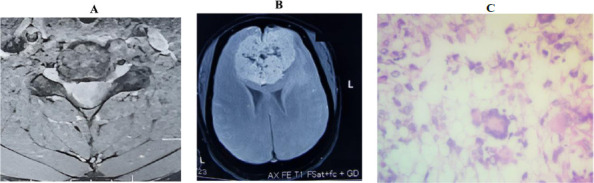

Results: This study of 338 patients with CNS tumours showed a slight female predominance (183 females, 155 males). The mean age was 38.1 years. Brain tumours were more common (290 cases) than spinal tumours (48 cases), with symptoms like headaches (44.44%) and visual disturbance (24.31%) prevalent in brain cases, and paraparesis (35.42%) and low back pain (16.67%) in spinal cases. Certain symptoms were strongly indicative of specific tumour types, such as seizures (OR: 3.3, CI: 1.6 - 6.9, p = 0.005) with meningiomas and visual disturbances with sellar tumours (OR: 6.7, CI: 3.6 - 12.9, p<0.001). Most tumours were low-grade (78.69%). Meningiomas were the most common (33.14%), particularly meningothelial (38.39%). Gliomas, glioneuronal, and neuronal tumours were next in prevalence (28.40%), followed by sellar tumours (18.93%). Astrocytomas (60.42%) were the predominant glioma subtype.

Conclusion: Low-grade tumours predominate in our setting. It is prudent that we channel efforts towards prompt diagnosis and treatment of such cases.